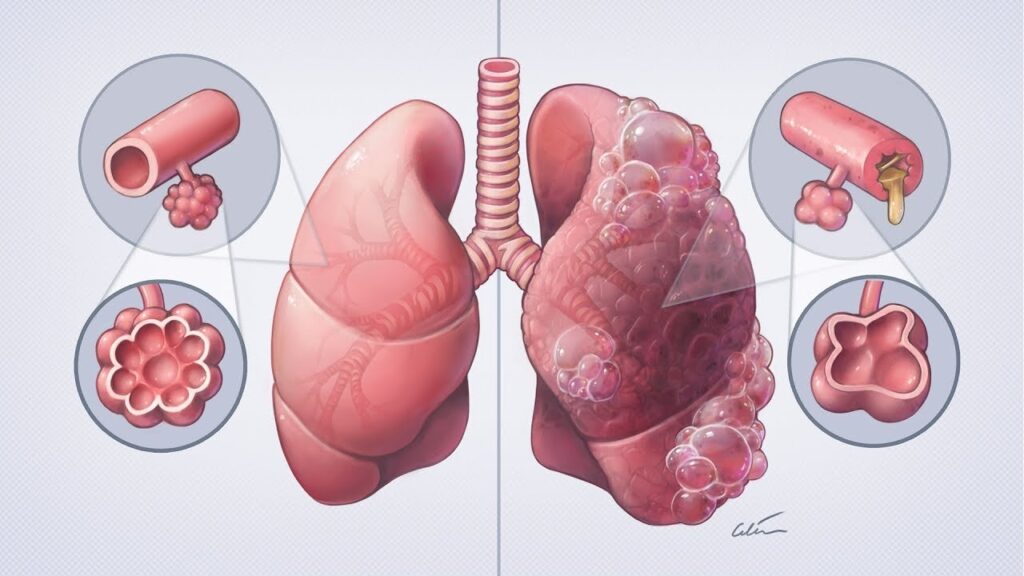

by Type:

- Chronic Bronchitis

- Emphysema